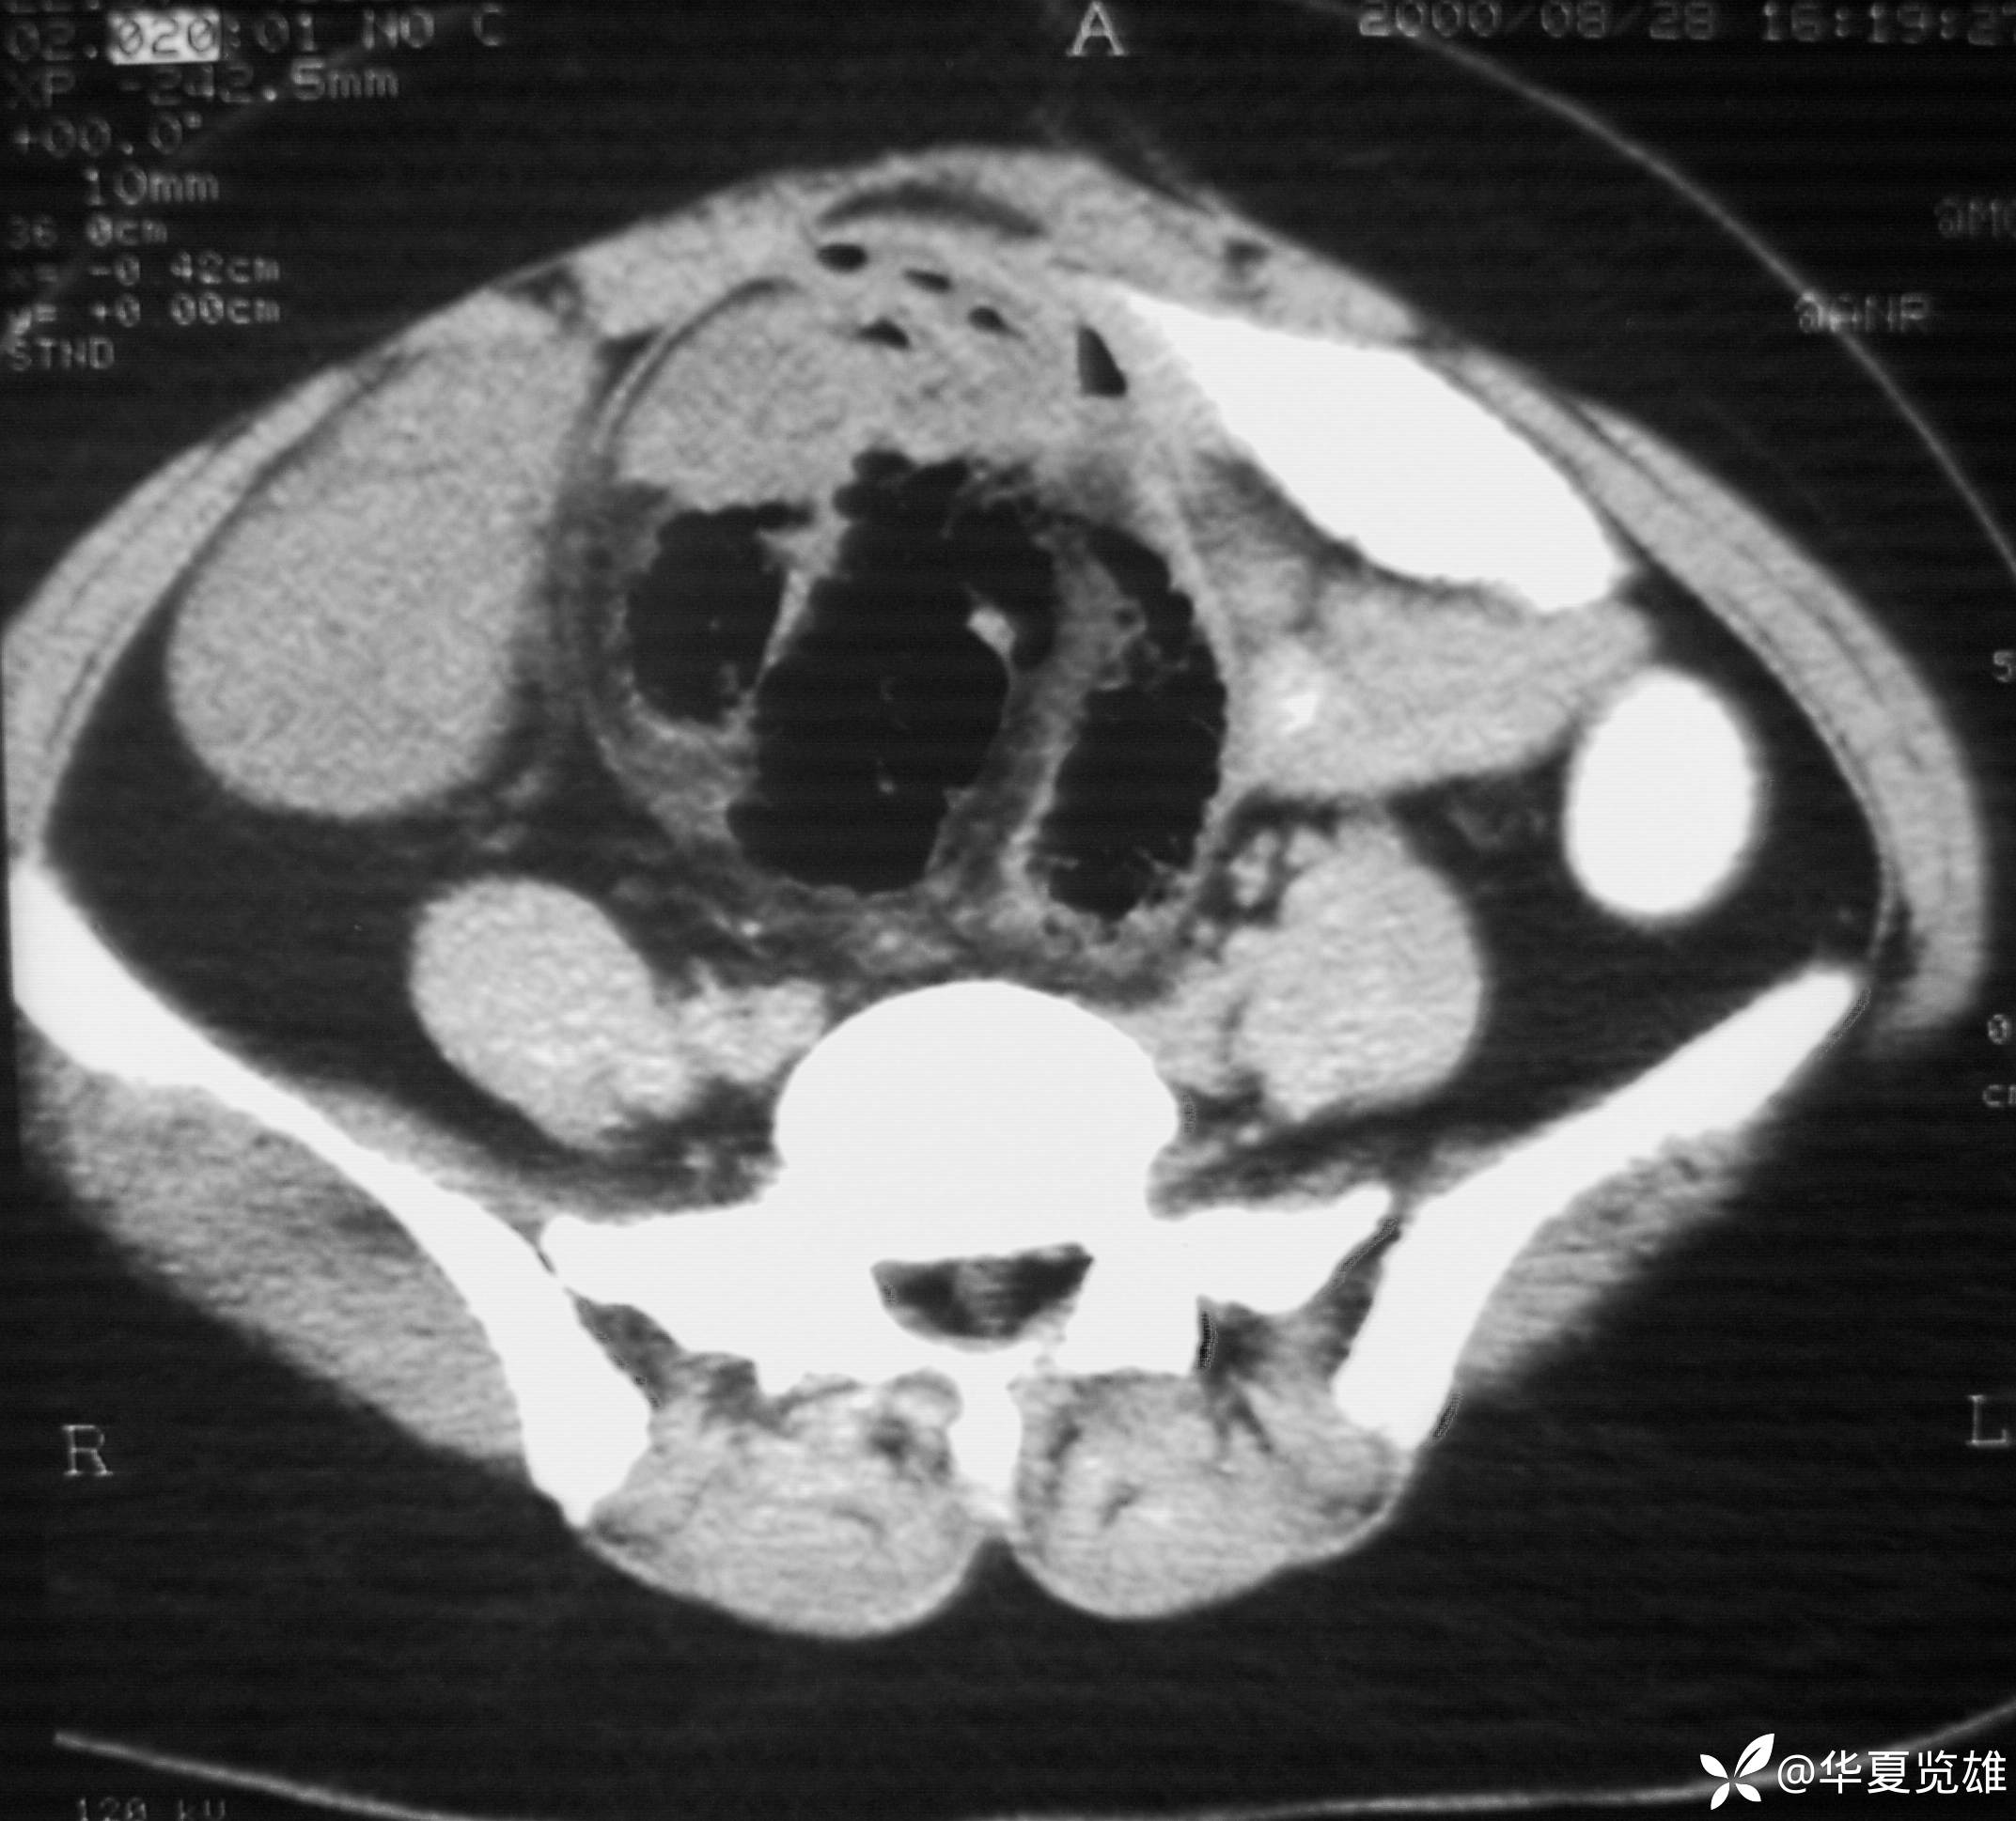

体格检查:下腹部有一纵形手术瘢痕。腹部压痛,无反跳痛。中下腹部扪及一12 cm× 18 cm包块,质韧,压痛。肠鸣音亢进,未闻及气过水音。

红箭-入口;绿箭-出口